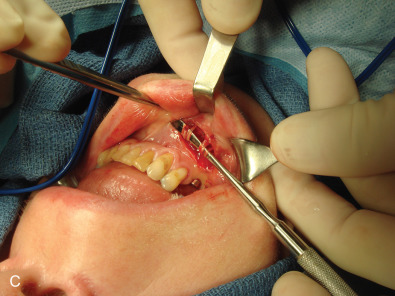

While the computed tomography (CT) scans usually cannot demonstrate nerves directly, the injury to a bone adjacent to the known anatomical location of a nerve supports the diagnosis of posttraumatic facial pain due to that nerve. This is demonstrated in Fig. 3.15.5A where the left orbital floor is lower than it is on the right, and the infraorbital canal is deformed on the left. In Fig. 3.15.5B , the right infraorbital nerve is injured at the location of the fixation plate at the infraorbital rim. Another example is given in Fig. 3.15.6 , where the right inferior alveolar nerve was injured twice; the first time with a screw designed to hold a bone graft prior to dental implant placement, and then a second time, when a metal clip was placed on the mental nerve at the mental foramen. The application of 3T MRI to the cranial nerves has brought a new dimension to being able to evaluate posttraumatic facial pain and is the best way to document vascular compression of the trigeminal ganglia and its roots.